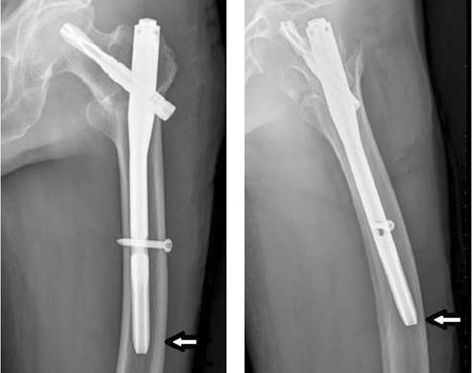

Гвоздь PFNA представляет собой специально разработанный интрамедуллярный стержень, используемый в ортопедической хирургии для стабилизации переломов проксимального отдела бедренной кости.Он состоит из длинного узкого металлического стержня, который вводится в интрамедуллярный канал бедренной кости от бедра до колена.Уникальная конструкция стержня PFNA обеспечивает стабильность вращения, способность распределять нагрузку и улучшает заживление переломов.

Гвоздь PFNA в первую очередь показан для лечения различных переломов бедра, включая межвертельные переломы, подвертельные переломы и некоторые переломы шейки бедра.Он особенно эффективен в тех случаях, когда требуется стабильная фиксация для обеспечения ранней нагрузки и подвижности.

Введение и фиксация гвоздя: Гвоздь PFNA осторожно вводят по проводнику, обеспечивая правильное выравнивание и избегая повреждения окружающих структур.Винты используются для фиксации гвоздя на месте.